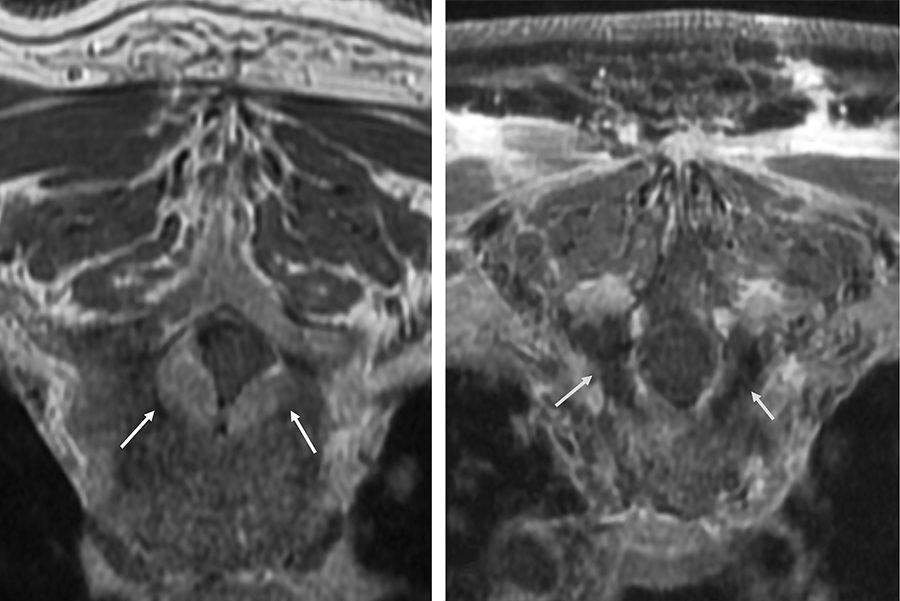

Tratamiento para el cáncer de mama sin cirugía